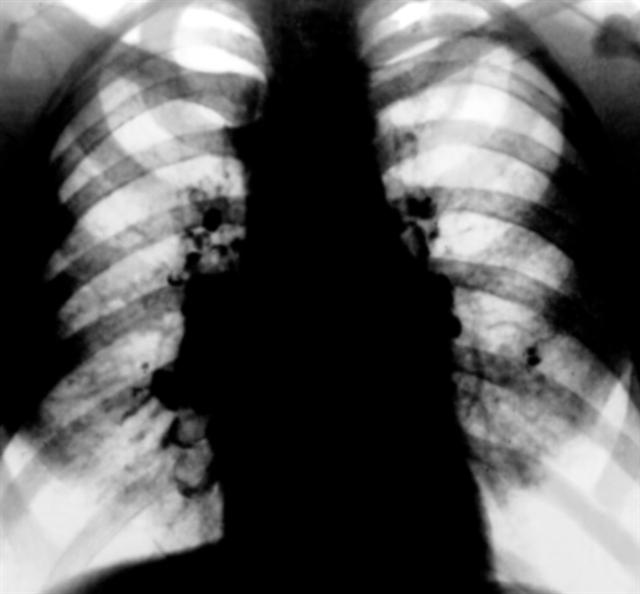

Рис. 3. Рентгенограмма грудной клетки при саркоидозе внутригрудных лимфатических узлов: тени легочных корней симметрично расширены, структура их резко изменена за счет сливающихся плотных крупных теней увеличенных лимфатических узлов.